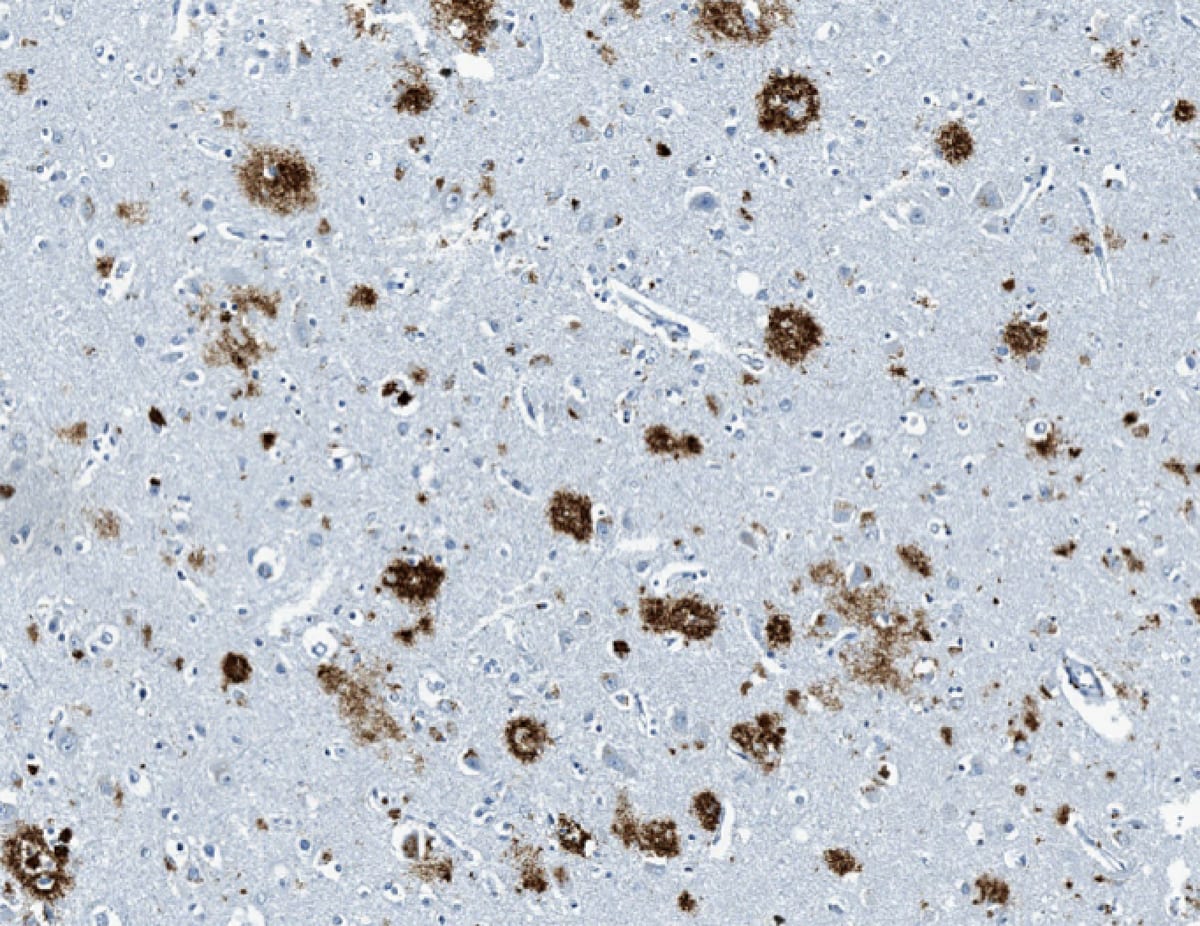

Pathology

- Microscopic analysis will show extracellular amyloid neuritic plaques and dystrophic neurites with reactive astrocytes and microglia.

- Intracellular neurofibrillary tangles, Hirano bodies, neuronal granulovacuolar degeneration, and the deposition of amyloid in the walls of blood vessels can also be seen.

- Neurofibrillary tangles: Flame-shaped intracellular inclusion bodies of phosphorylated tau protein.

- Hirano bodies: Intracellular aggregates of actin and actin-associated proteins, which are not specific to Alzheimer’s disease.

- Granulovacuolar degeneration: Intraneuronal accumulation of large (up to 5 µm diameter) double membrane-bound vacuoles harboring a central granule.